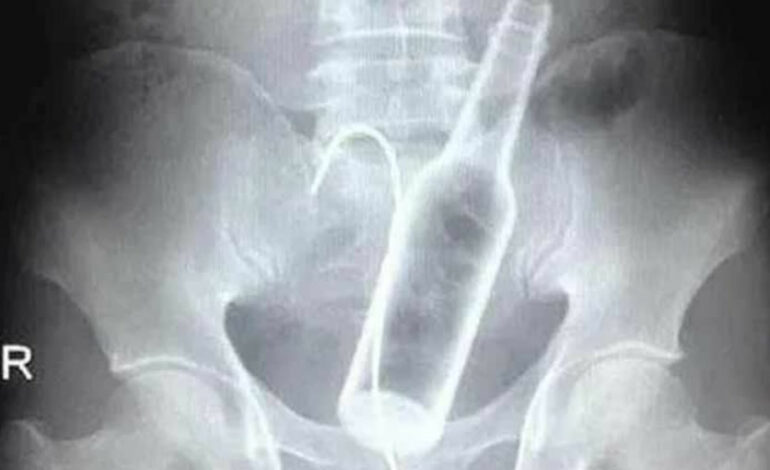

Neste fim de semana um caso um tanto inusitado ocorreu no município de Brasiléia, no interior do Acre, um rapaz de 25 anos, que não teve o nome revelado, acabou introduzindo uma garrafa de cerveja no ânus, durante bebedeira com amigos.

No entanto, a brincadeira não deu certo e o homem teve que ser socorrido pelo Serviço Móvel de Urgência e Emergência (Samu) que, imediatamente, levou o jovem para o Hospital de Brasiléia, mas, a equipe não conseguiu retirar o objeto e tiveram que realizar a transferência para o Pronto-Socorro de Rio Branco.

Após avaliação clínica, o rapaz foi submetido a uma cirurgia para remoção da garrafa. Após o episódio, ele se recupera bem.